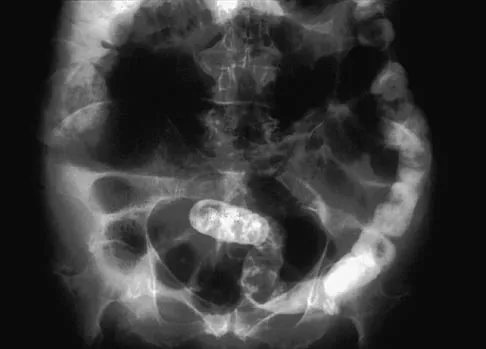

A 65-year-old woman has nausea, vomiting, and abdominal distention after undergoing total knee arthroplasty 48 hours ago. An abdominal radiograph is shown in Figure 14. Associated risk factors for this disorder include

Explanation

The prevalence of postoperative ileus associated with total joint arthroplasty has been reported to be as high as 3%. Metabolic abnormalities such as hypokalemia are believed to contribute to the onset of ileus and Ogilvie's syndrome (acute pseudo-obstruction of the colon). Prolonged bed rest also has been associated with the development of ileus and Ogilvie's syndrome. Untreated Ogilvie's syndrome can result in cecal perforation. Ileus usually is not accompanied by mechanical obstruction. Antibiotic administration and the type of anesthesia used have not been correlated with development of ileus. Administration of warfarin has been associated with elevated prothrombin time/partial thromboplastin time and international normalized ratio levels when ileus is managed with a nasogastric tube and suction. Metabolic imbalances must be corrected to reverse the ileus process. Iorio R, Healy WL, Appleby D: The association of excessive warfarin anticoagulation and postoperative ileus after total joint replacement surgery. J Arthroplasty 2000;15:220-223.

References:

- Clarke HD, Berry DJ, Larson DR: Acute pseudo-obstruction of the colon as a postoperative complication of hip arthroplasty. J Bone Joint Surg Am 1997;79:1642-1647.